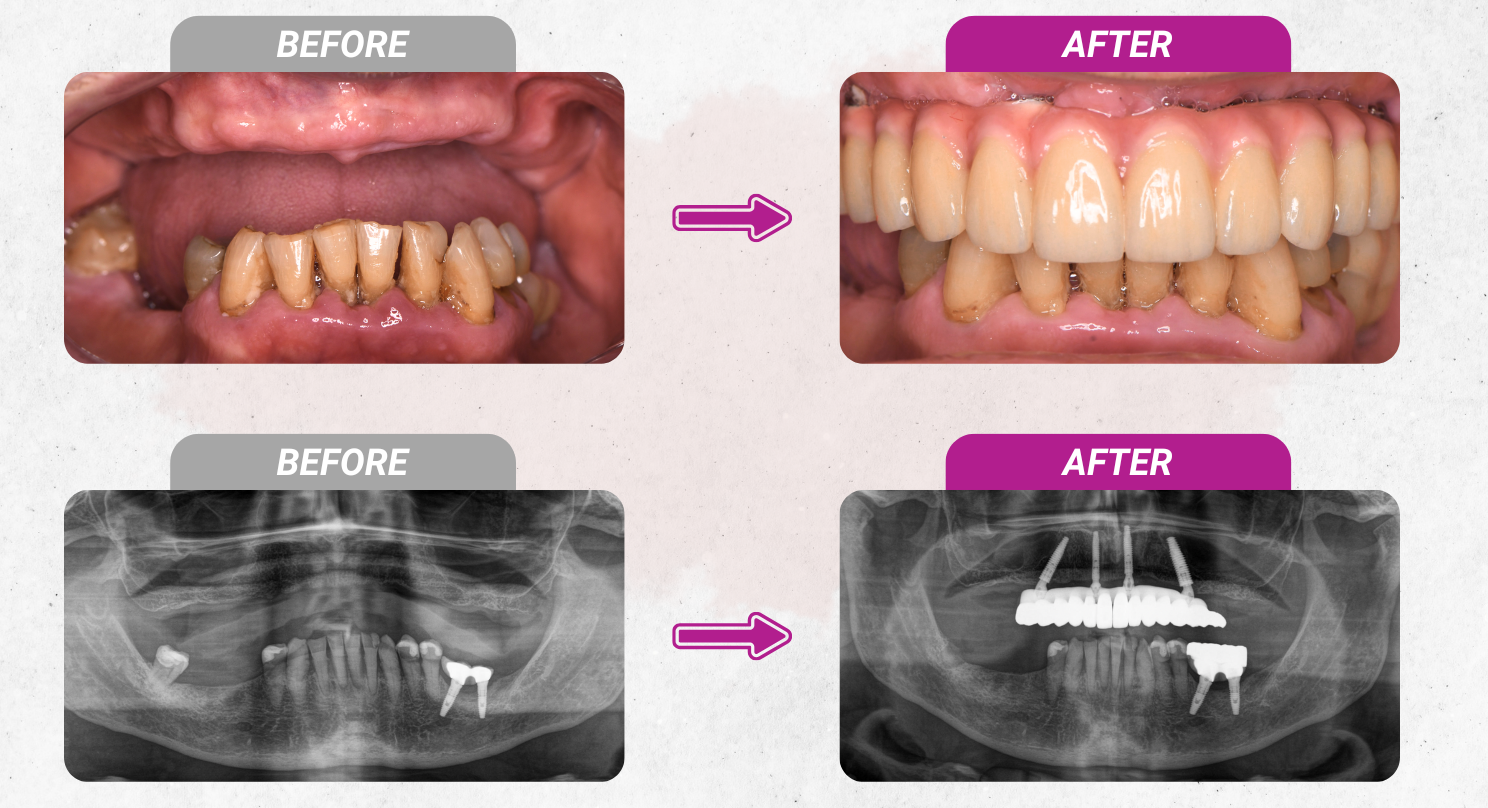

All-on-X Full Arch Implant is a method of implanting 4-6 implants in the favorable direction of the jawbone to make a solid pillar, helping to support the restoration of the 12-14 upper teeth. Thereby, it helps restore teeth for patients who have lost many teeth, are about to lose their entire teeth or lose their entire jaw (mainly occurring in middle age or the elderly).

Currently, there are 2 popular full-jaw implant options, All-on-4 and All-on-6.